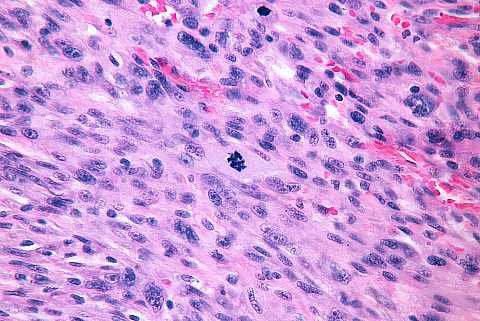

High power view near the surface. Cytologically malignant spindle and epithelioid cells are present: